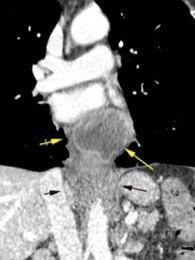

Aneurisma aórtico intracrural

/Restrepo CS et al. The diaphragmatic crura and retrocrural space: normal imaging appearance, variants, and pathologic conditions. Radiographics 2008